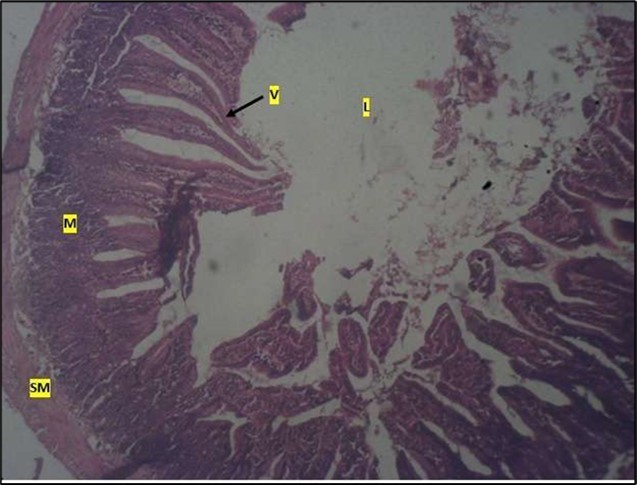

Micrographs of The Small Intestine

Histological examination of the small intestine result in control animals revealed a normal architecture with the red pulp and white pulp with no pathological observation Figure 2. Administration of Abelmoschus esculentus at low dose shows an increased cellularity with numerous cells in the Mucosa and the villi projecting towards the lumen. Focal metaplasia of mucosal cells alongside villous disruption was also observed (Figure 3). The high dose group showed normal cellular architecture with no villous disruption (Figure 4).

Figure 4.High dose showing a normal mucosa (m) with villi (v) projecting towards the lumen(l) and underlying smooth muscle layer (sm). No pathology seen